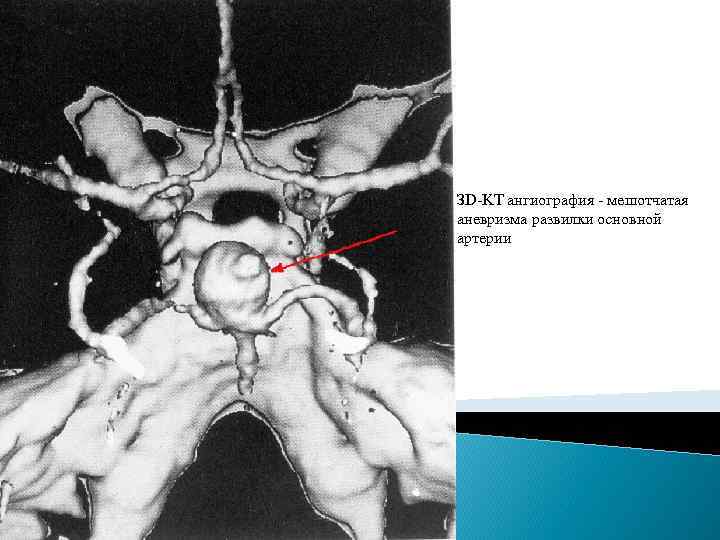

Классификация аневризм. Существует множество классификаций аневризм головного мозга, наиболее распространенные из них – классификация по форме, величине и артерии, на которой они расположены. Классификация аневризмы по форме. 1. Мешотчатые (одно- или многокамерные). 2. Веретенообразные (фузиформные). Классификация аневризм по артерии, на которой они расположены. 1. На передней мозговой – передней соединительной артериях (45 %). 2. На внутренней сонной артерии (32%). 3. На средней мозговой артерии (19%). 4. На артериях вертебро-базилярной системы (4%) 5. Множественные аневризмы – на двух и более артериях (13%). Классификация аневризм по величине. 1. До 3 мм – милиарные. 2. 4 - 15 мм – обычные. 3. 16 - 25 мм – большие. 4. Более 25 мм – гигантские.

ЗD-KT ангиография - мешотчатая аневризма развилки основной артерии